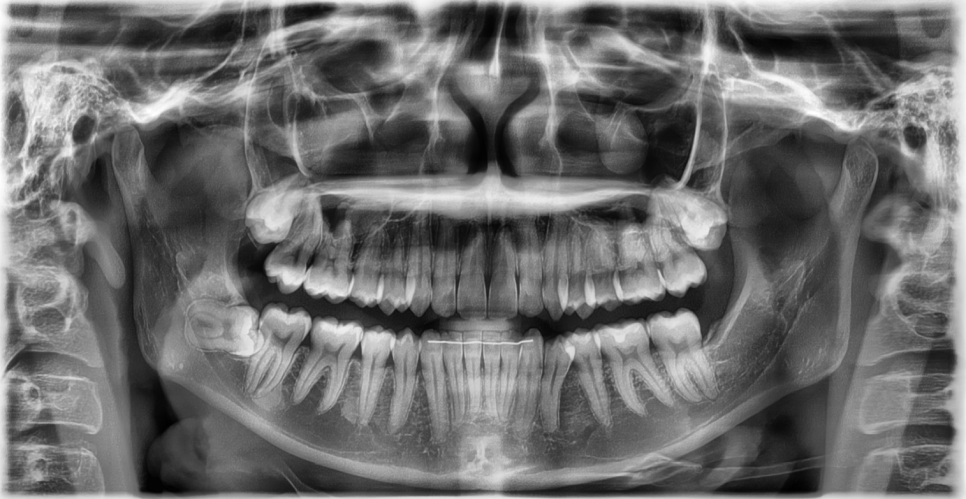

특히 매복 사랑니,

혹은 비스듬히 누워 있는 사랑니라면

앞쪽 어금니까지 영향을 주는 경우도 많습니다.

이 경우

사랑니 하나 문제가 아니라

멀쩡하던 어금니 치료까지 이어질 수 있습니다.

실제 치아 상태,

잇몸 속 위치,

신경과의 거리,

웃거나 씹을 때 사용하는 범위까지

직접 확인해야 정확한 판단이 가능합니다.